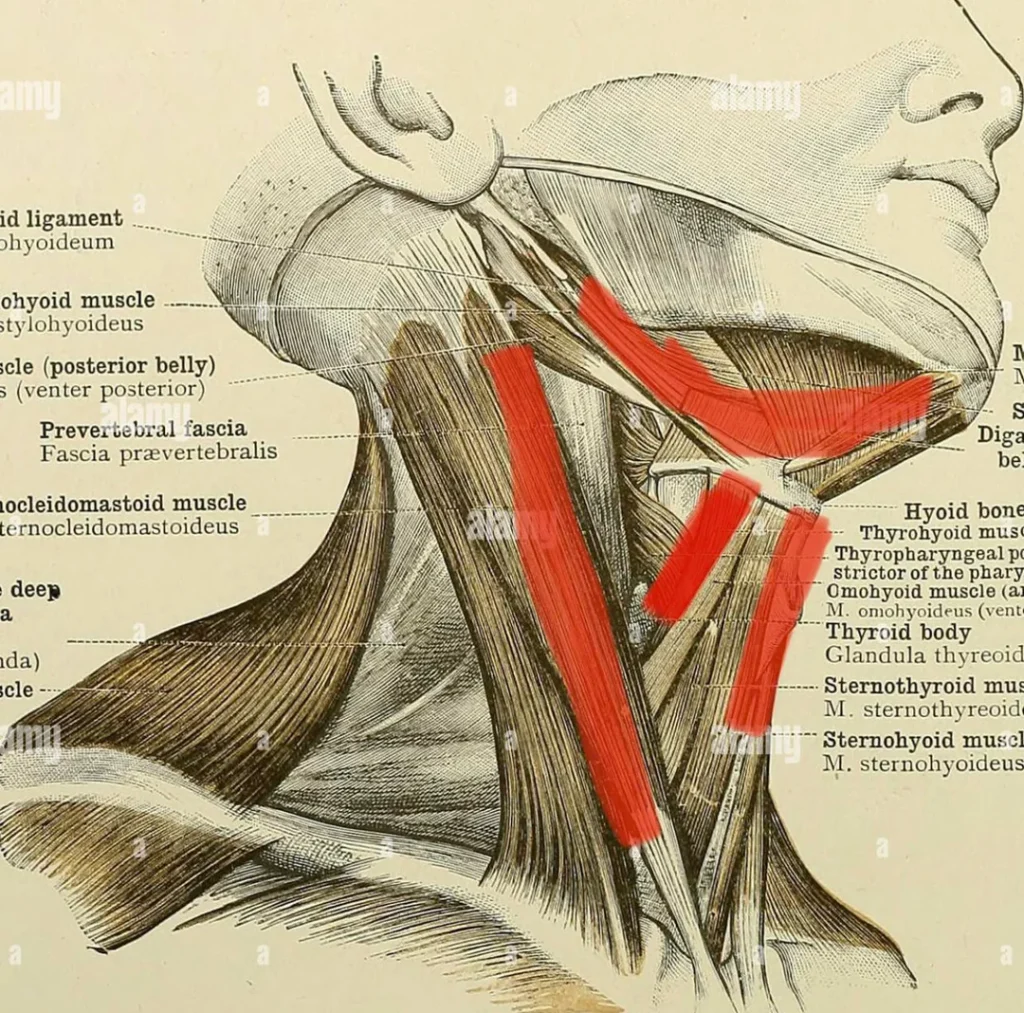

The Digastric Muscle Issues & Acupuncture Treatment in Tokyo

The human body is a marvel of interconnected systems, and muscles play a pivotal role in movement, stability, and function. Among these, the digastric muscle, though small, is a critical component of head and neck movement, particularly in activities like speaking, swallowing, and chewing. This article delves into the anatomy, function, common issues, and treatment […]